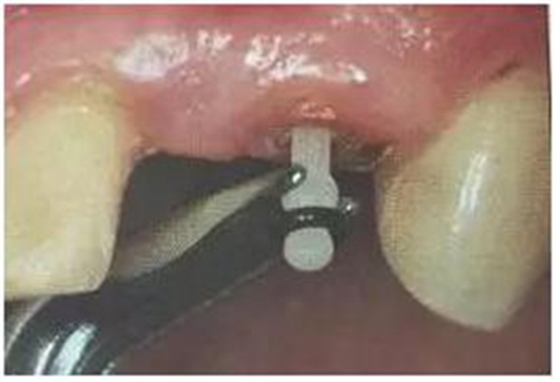

2. 清除根管壁殘留物

根管壁殘留物的存在直接影響纖維樁的粘接和固位,這也是導(dǎo)致纖維樁脫落的主要原因。

(根管內(nèi)殘留物)

個(gè)人見解:必要的情況下先開闊根管口建立一定的視角后,慢速手機(jī)上G鉆為引導(dǎo)鉆,由號遞增引導(dǎo)開闊通路;P鉆預(yù)備樁道,同樣需要由小向大號遞增,直到選擇好適合的號預(yù)備到規(guī)定測量的深度即可,再配合纖維樁系統(tǒng)中各型號纖維樁所匹配的樁道

鉆,預(yù)備、修整成與纖維樁相適應(yīng)的樁道。

預(yù)備后根管壁上會(huì)不同程度的牙膠和封閉劑等殘留物,所以樁道預(yù)備前后建議X線片輔助檢查預(yù)備深度等情況,而殘留物也會(huì)很清晰地顯現(xiàn)。

根管銼去除殘留物,很難去除干凈,而備取樁道時(shí),禁止使用牙膠溶解劑(如:丁克除、氯仿)等有機(jī)溶劑去除殘留物,以防破壞根尖區(qū)牙膠的封閉和防止附著根管壁影響粘接。(超聲去除根管殘留物)

通常此時(shí)以超聲潔牙機(jī)更換較細(xì)工作尖進(jìn)入根管(根管消毒沖洗液配合清潔工作后面會(huì)提到),徹底去除樁道根管壁上的附著殘留物,效果明顯。再配合X線片、根管顯微鏡輔助檢查清理的情況下更佳。